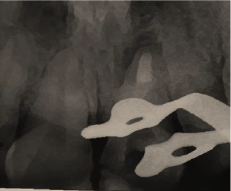

Figure 1b. A preoperative periapical radiograph of maxillary central region: observe open apex of tooth 21 with radiolucent area

Clinical examination (figure 1a) revealed defective resin composite restoration on teeth #21 and #11. Tooth#21 showed an access cavity already done, with a clear discoloration. Sensitivity tests showed positive response only on tooth #11. The tooth #21 was tender to percussion with a physiological mobility. The periodontal state was unhealthy. The gingiva was inflamed with plaque and calculus on teeth. Periapical radiographic examination (figure 1b) showed an immature open apex of the tooth #21 with a radiolucent lesion in the apical area.

Figure 1a. Initial clinical view of the anterior maxillary region: observe the defective restorations of teeth 11 and 21 with discoloration on tooth 21.